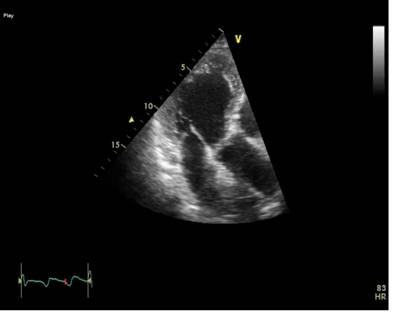

Ecocardiografie : evidentiaza ventricul stang cu dimensiuni la limita superioara a normalului cu disfunctie sistolica severa de ventricul stang (FEVS 30%), prezentand hipokinezie difuza pe peretii VS, dilatare usoara de Ao asc ( 44mm), hipertensiune pulmonara moderata- PAP sistolica 55 mmHg.(Fig. 3, 4,5).

Fig. 4 Sectiune apicala 3 camere -hipokinezie sept anterior si perete infero-lateral fisier HERA 35 movie